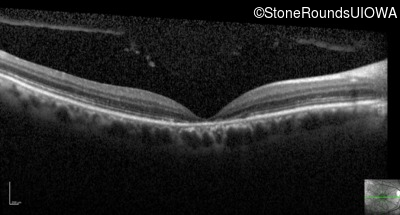

Optical Coherence Tomography - Right - 20/125

Exemplar / OCT Stack

OCT Stack